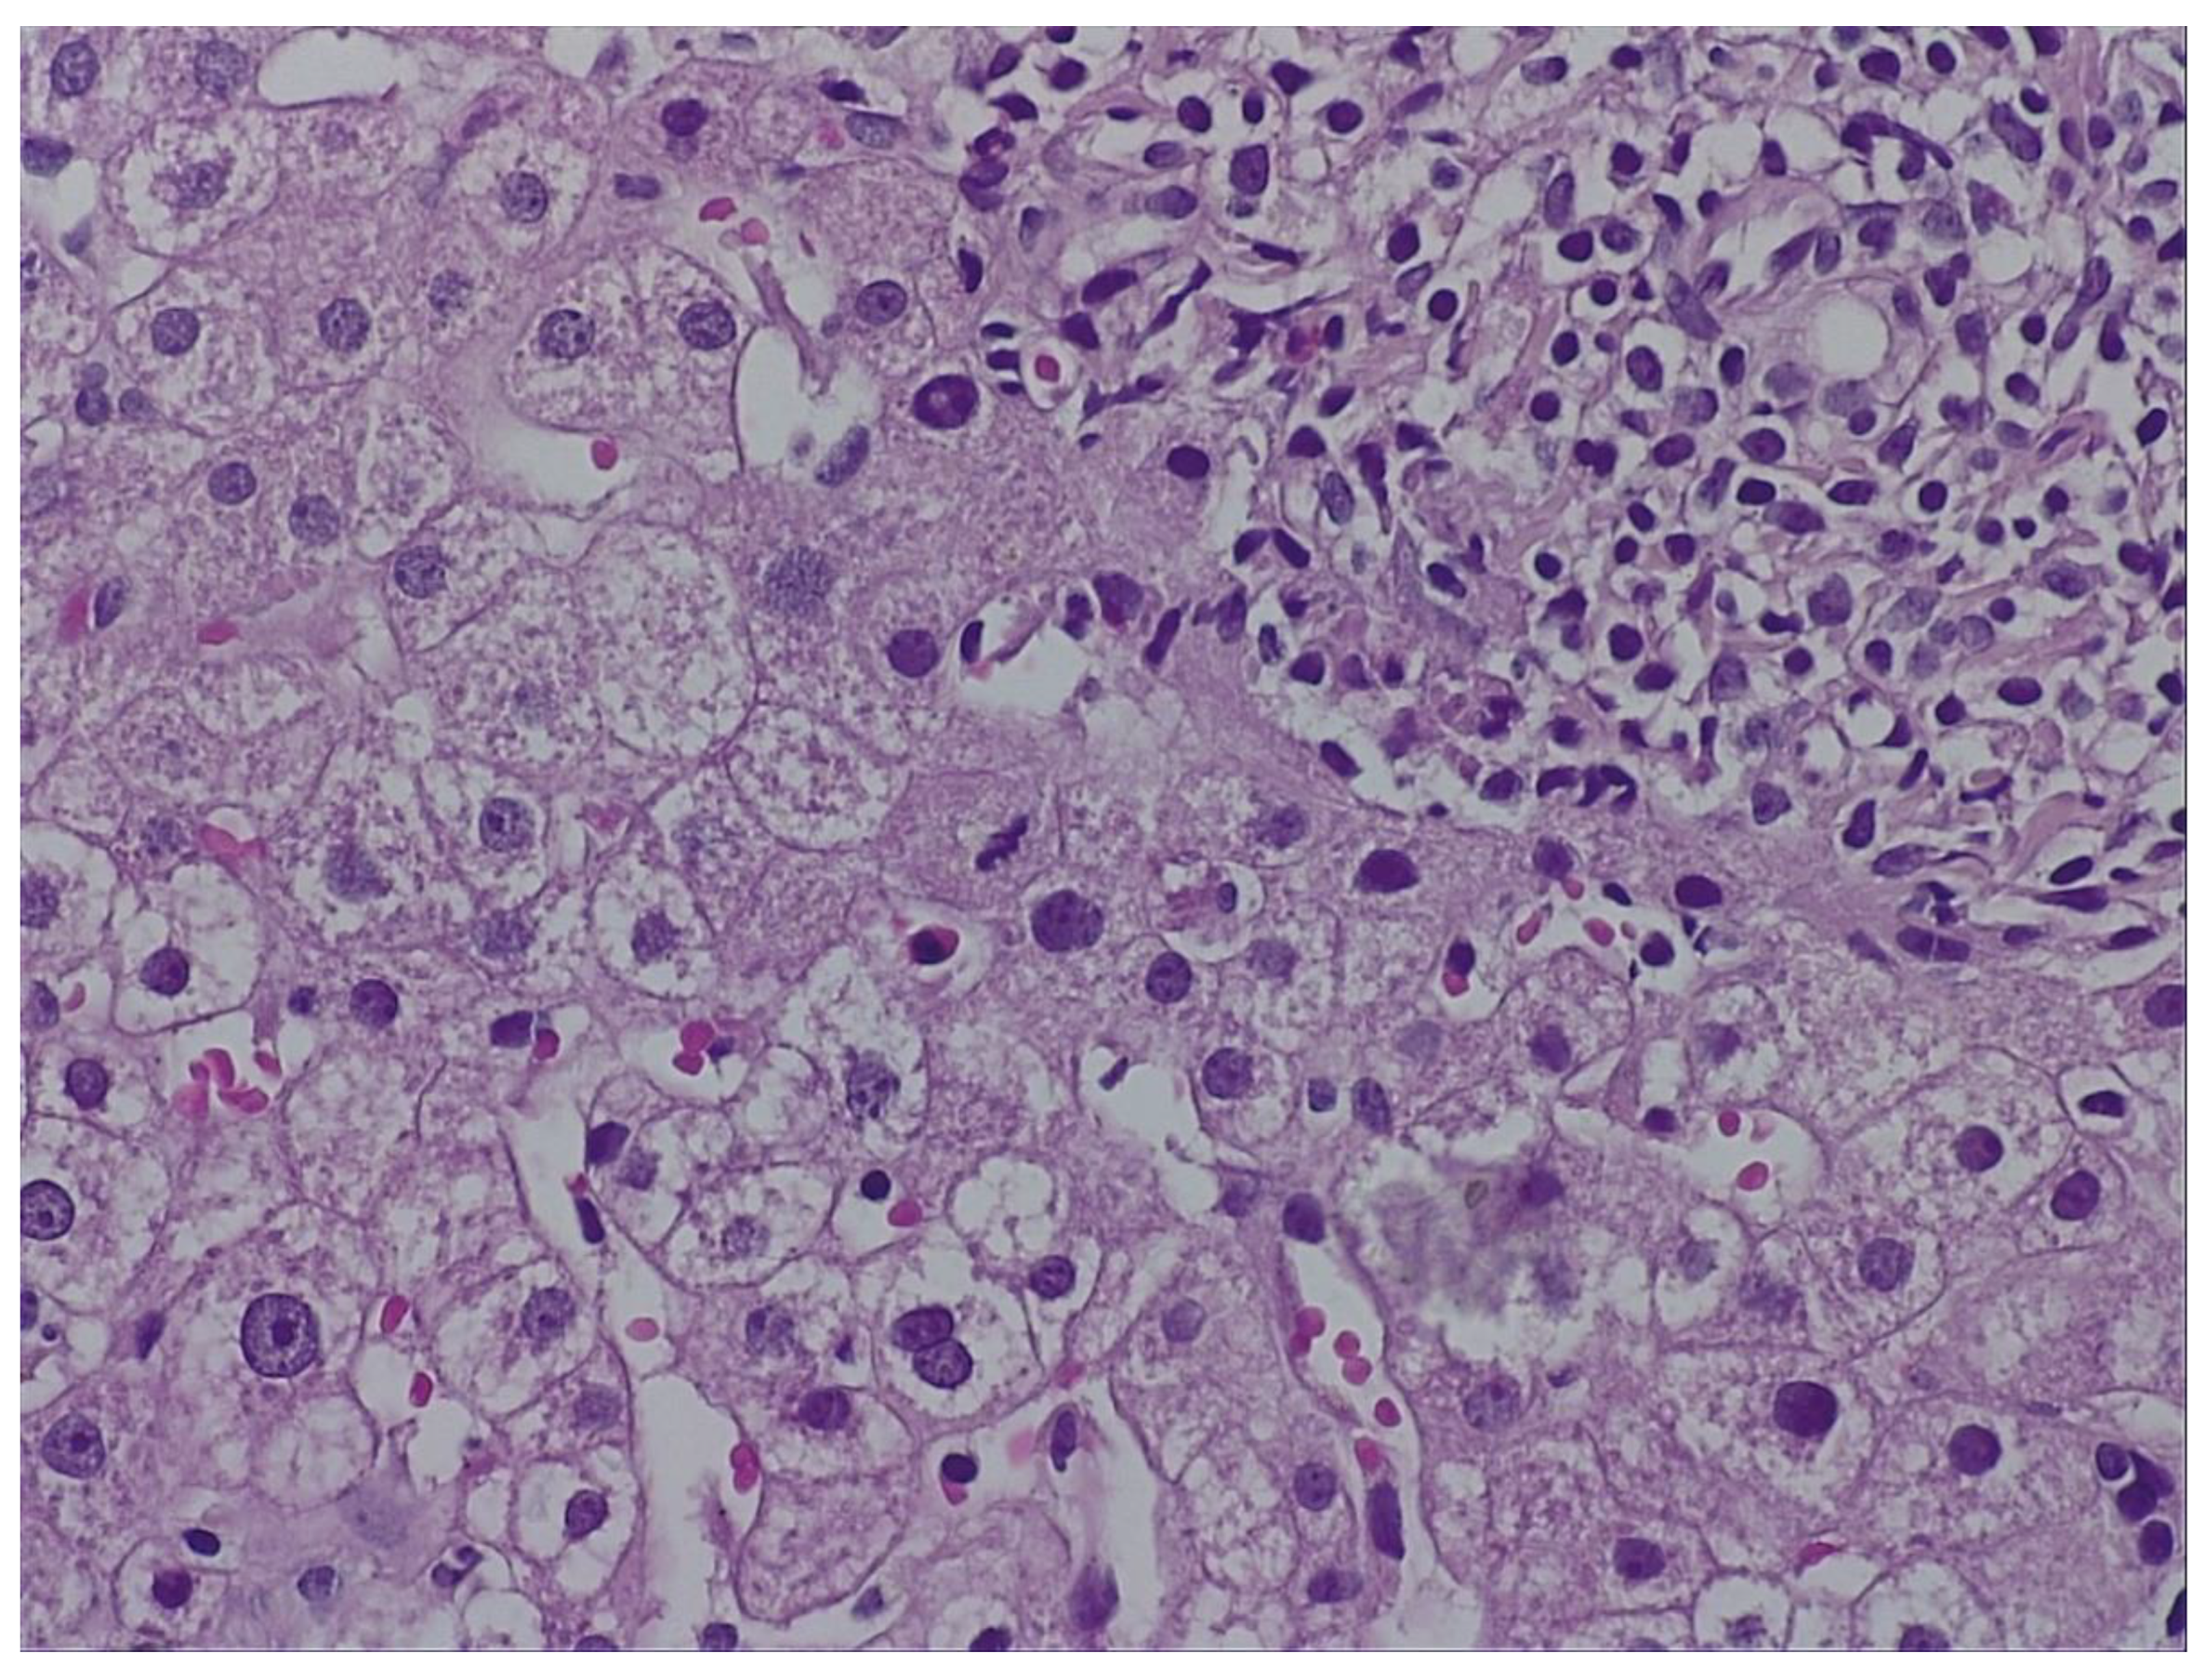

During hospitalization, the patient received hepatoprotective therapy consisting of silymarin, essential phospholipids and amino-acids, and L-arginine, alongside solutions for metabolic support and hydro-electrolytic rebalancing. Initial favorable clinical evolution allowed discharge; however, the patient re-presented to the hospital a few days post-discharge due to symptom recurrence. To establish the etiopathogenesis of the hepatocitolytic syndrome, a liver biopsy was performed. Histology described mild-to-moderate portal tract expansion with lymphoplasmocytic inflammation, preserved portal triad without pathological fibrosis and without interface hepatitis. Numerous apoptotic hepatocytes and focal confluent necrosis were noted, but without bridging necrosis. No histological signs of cholestasis or steatosis were identified. The overall picture was that of moderate-to-severe portal and lobular hepatitis without specific features; therefore, a possible herb-induced liver injury (HILI) could not be excluded. (Figure 1 and Figure 2.)

„The biopsy core measures 14 mm in length and, on histological sections, is thin but adequate, showing preserved lobular architecture of the hepatic parenchyma. Two portal tracts and seven centrilobular veins are identified. The portal tracts are mildly to moderately expanded with lymphoplasmacytic inflammatory infiltrate; the portal triad is preserved, without pathological fibrosis and without interface hepatitis. Within the lobules, there is hepatocellular ballooning (dystrophic change), numerous apoptotic hepatocytes, focal and confluent necrosis without bridging necrosis; frequent typical mitoses and regenerative hepatocellular rosettes are also noted. There is no histological evidence of cholestasis or pathological steatosis.” Histopathological interpretation corresponding to Figure 1 and Figure 2.

Figure 2. Biopsy fragment – H&E staining.